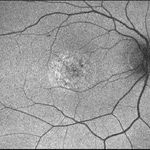

"Mud-Splatter" of Posterior Pole and Peripheral Radial Streaks in a Carrier of Ocular Albinism

14-year-old healthy white female with family history of ocular albinism was seen by Dr. Hruby for a second opinion. Father and some of his brothers were positive for a history of ocular albinism. Va cc 20/30 J1+ OU; no nystagmus; no TIDs; no foveal hypoplasia. A "mud-spatter" appearance to the posterior pole was present, along with peripheral alternating streaks. Hypoautofluorescent areas correspond to hyperpigmented areas of retinal pigment epithelium, and vice versa (see photo). Dr. Hruby agreed that this was most likely a carrier of Ocular Albinism Type-1 (XR; GPR143 mutation), and possible genetic testing/counselling was discussed.

Photographer: Gretchen Harper

Imaging device: Optos California

Condition/keywords: Nettleship-Falls ocular albinism, ocular albinism